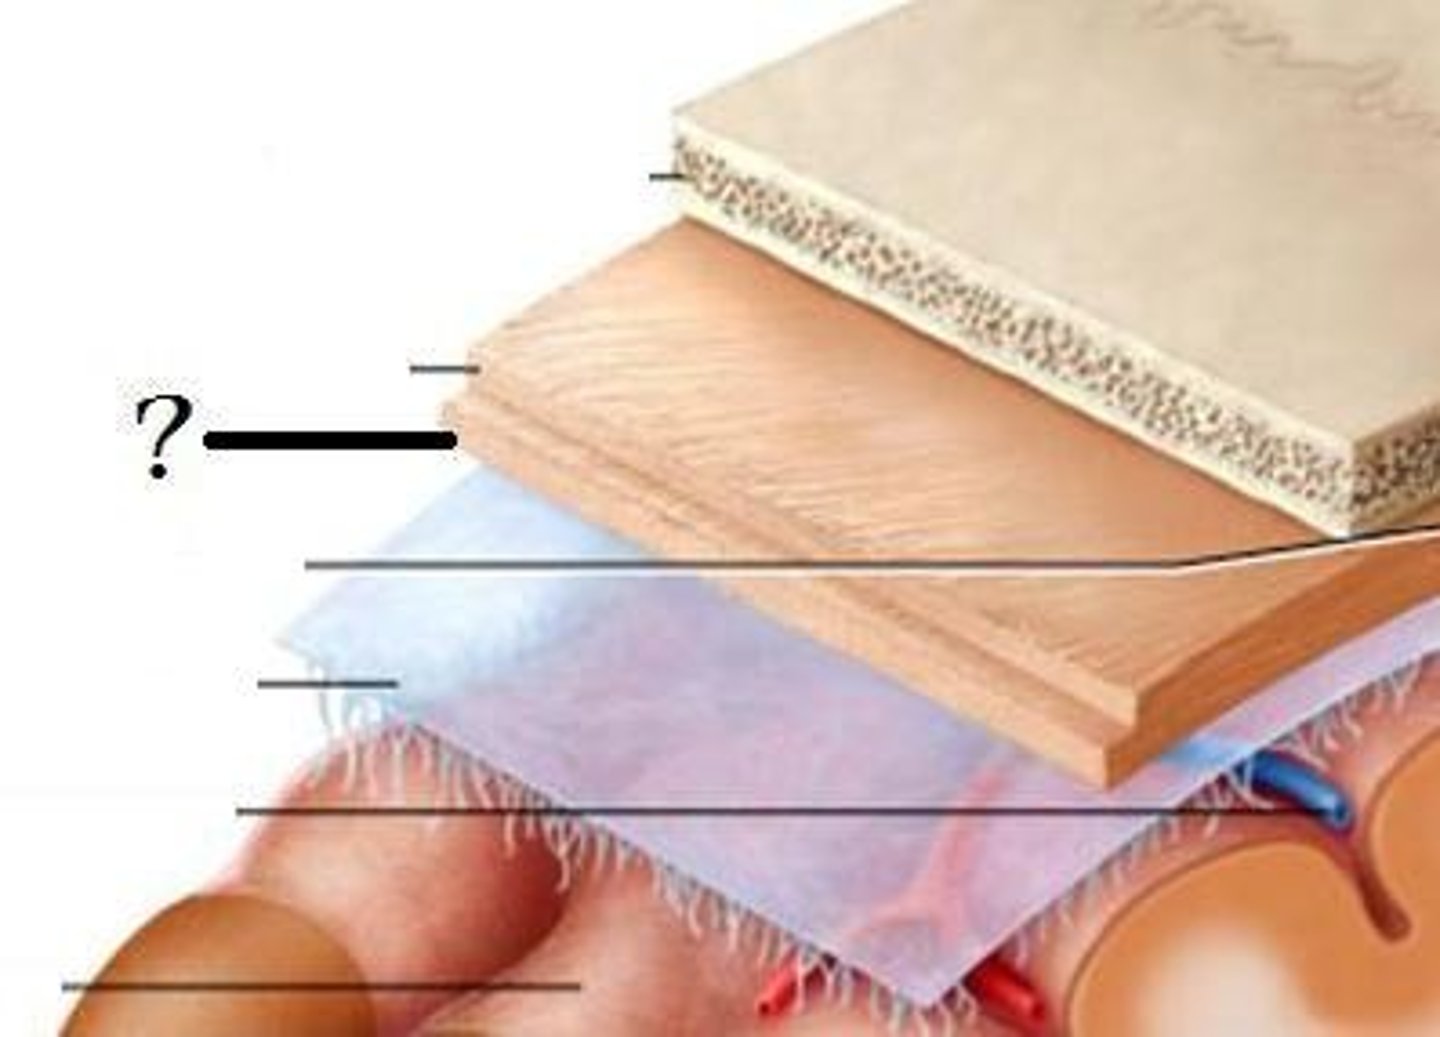

meninges function

protect brain and spinal cord

pia mater

deepest meninge, follows every contour of the brain

arachnoid mater

middle meninge, collagen and elastin fiber, spider web look

dura mater

made up of tough fibrous connective tissue, made up of the periosteal layer (creates periosteum of skull bone)

subarachnoid space

filled with cerebrospinal fluid

subdural space

below the dura mater

potential space (if you have a head injury

the blood goes into the subdural space)